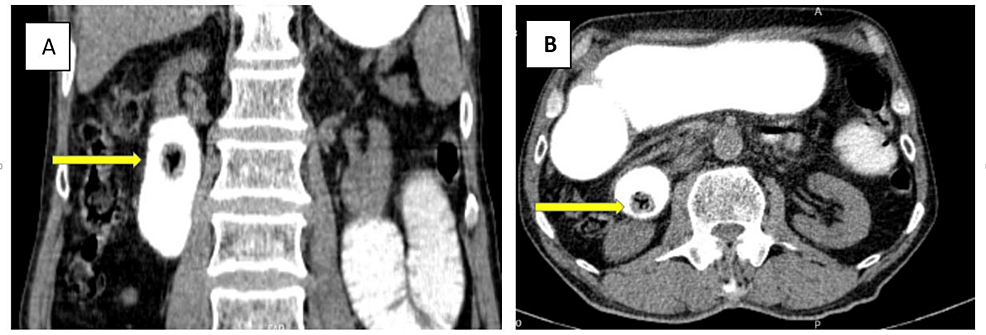

On the fifth postoperative day, after beginning an oral diet, mild colicky abdominal pain and bilious vomiting were revealed. A second abdominopelvic CT scan with oral contrast was performed, which demonstrated another duodenal ectopic non-obstructing gallbladder stone measuring 17 x 15 mm with a typical Mercedes-Benz sign in favor of recently migrated gall stone (Figure 3). Since the patient had no obstructive symptoms, conservative treatment and follow-up were opted for.

As mentioned before, our patient underwent enterolithotomy alone, and the main reasons for preferring this approach were severe inflammatory changes and many adhesions around the gallbladder, which increased the risk of iatrogenic injuries. Also, the patient’s advanced age, presence of comorbidities, and poor compliance played a role in this decision. In the case of the second ectopic stone, which was detected in the follow-up CT scan, we preferred conservative treatment over re-enterolithotomy due to the stone size and absence of clear obstruction signs, and it passed through the GI tract, fortunately. CT scan had a significant role in our decision-making, as it enabled us to estimate the size and location of the stone and choose the non-surgical option for treatment.

Nowadays, the advanced manifestations of gallstone disease have considerably declined due to early diagnosis and treatment. Gallstone ileus should be considered when encountering a case of small bowel obstruction, especially in elderly individuals with a positive history of cholelithiasis. The best surgical option for gallstone ileus is still a subject of controversy. Due to the low risk of complications, enterolithotomy alone is the most popular surgical procedure. In our case, the delay in surgery due to patient refusal, his general clinical condition, the patient’s advanced age, as well as extensive adhesion and inflammatory changes of the gallbladder and the duodenal wall prompted us to opt for enterolithotomy alone. CT scan is a readily available, quick, and high-resolution diagnostic modality, which, due to its high diagnostic accuracy, plays a decisive role both in the diagnosis and in determining the treatment plans. In our case, the findings of the CT scan enabled us to avoid performing re-surgery.